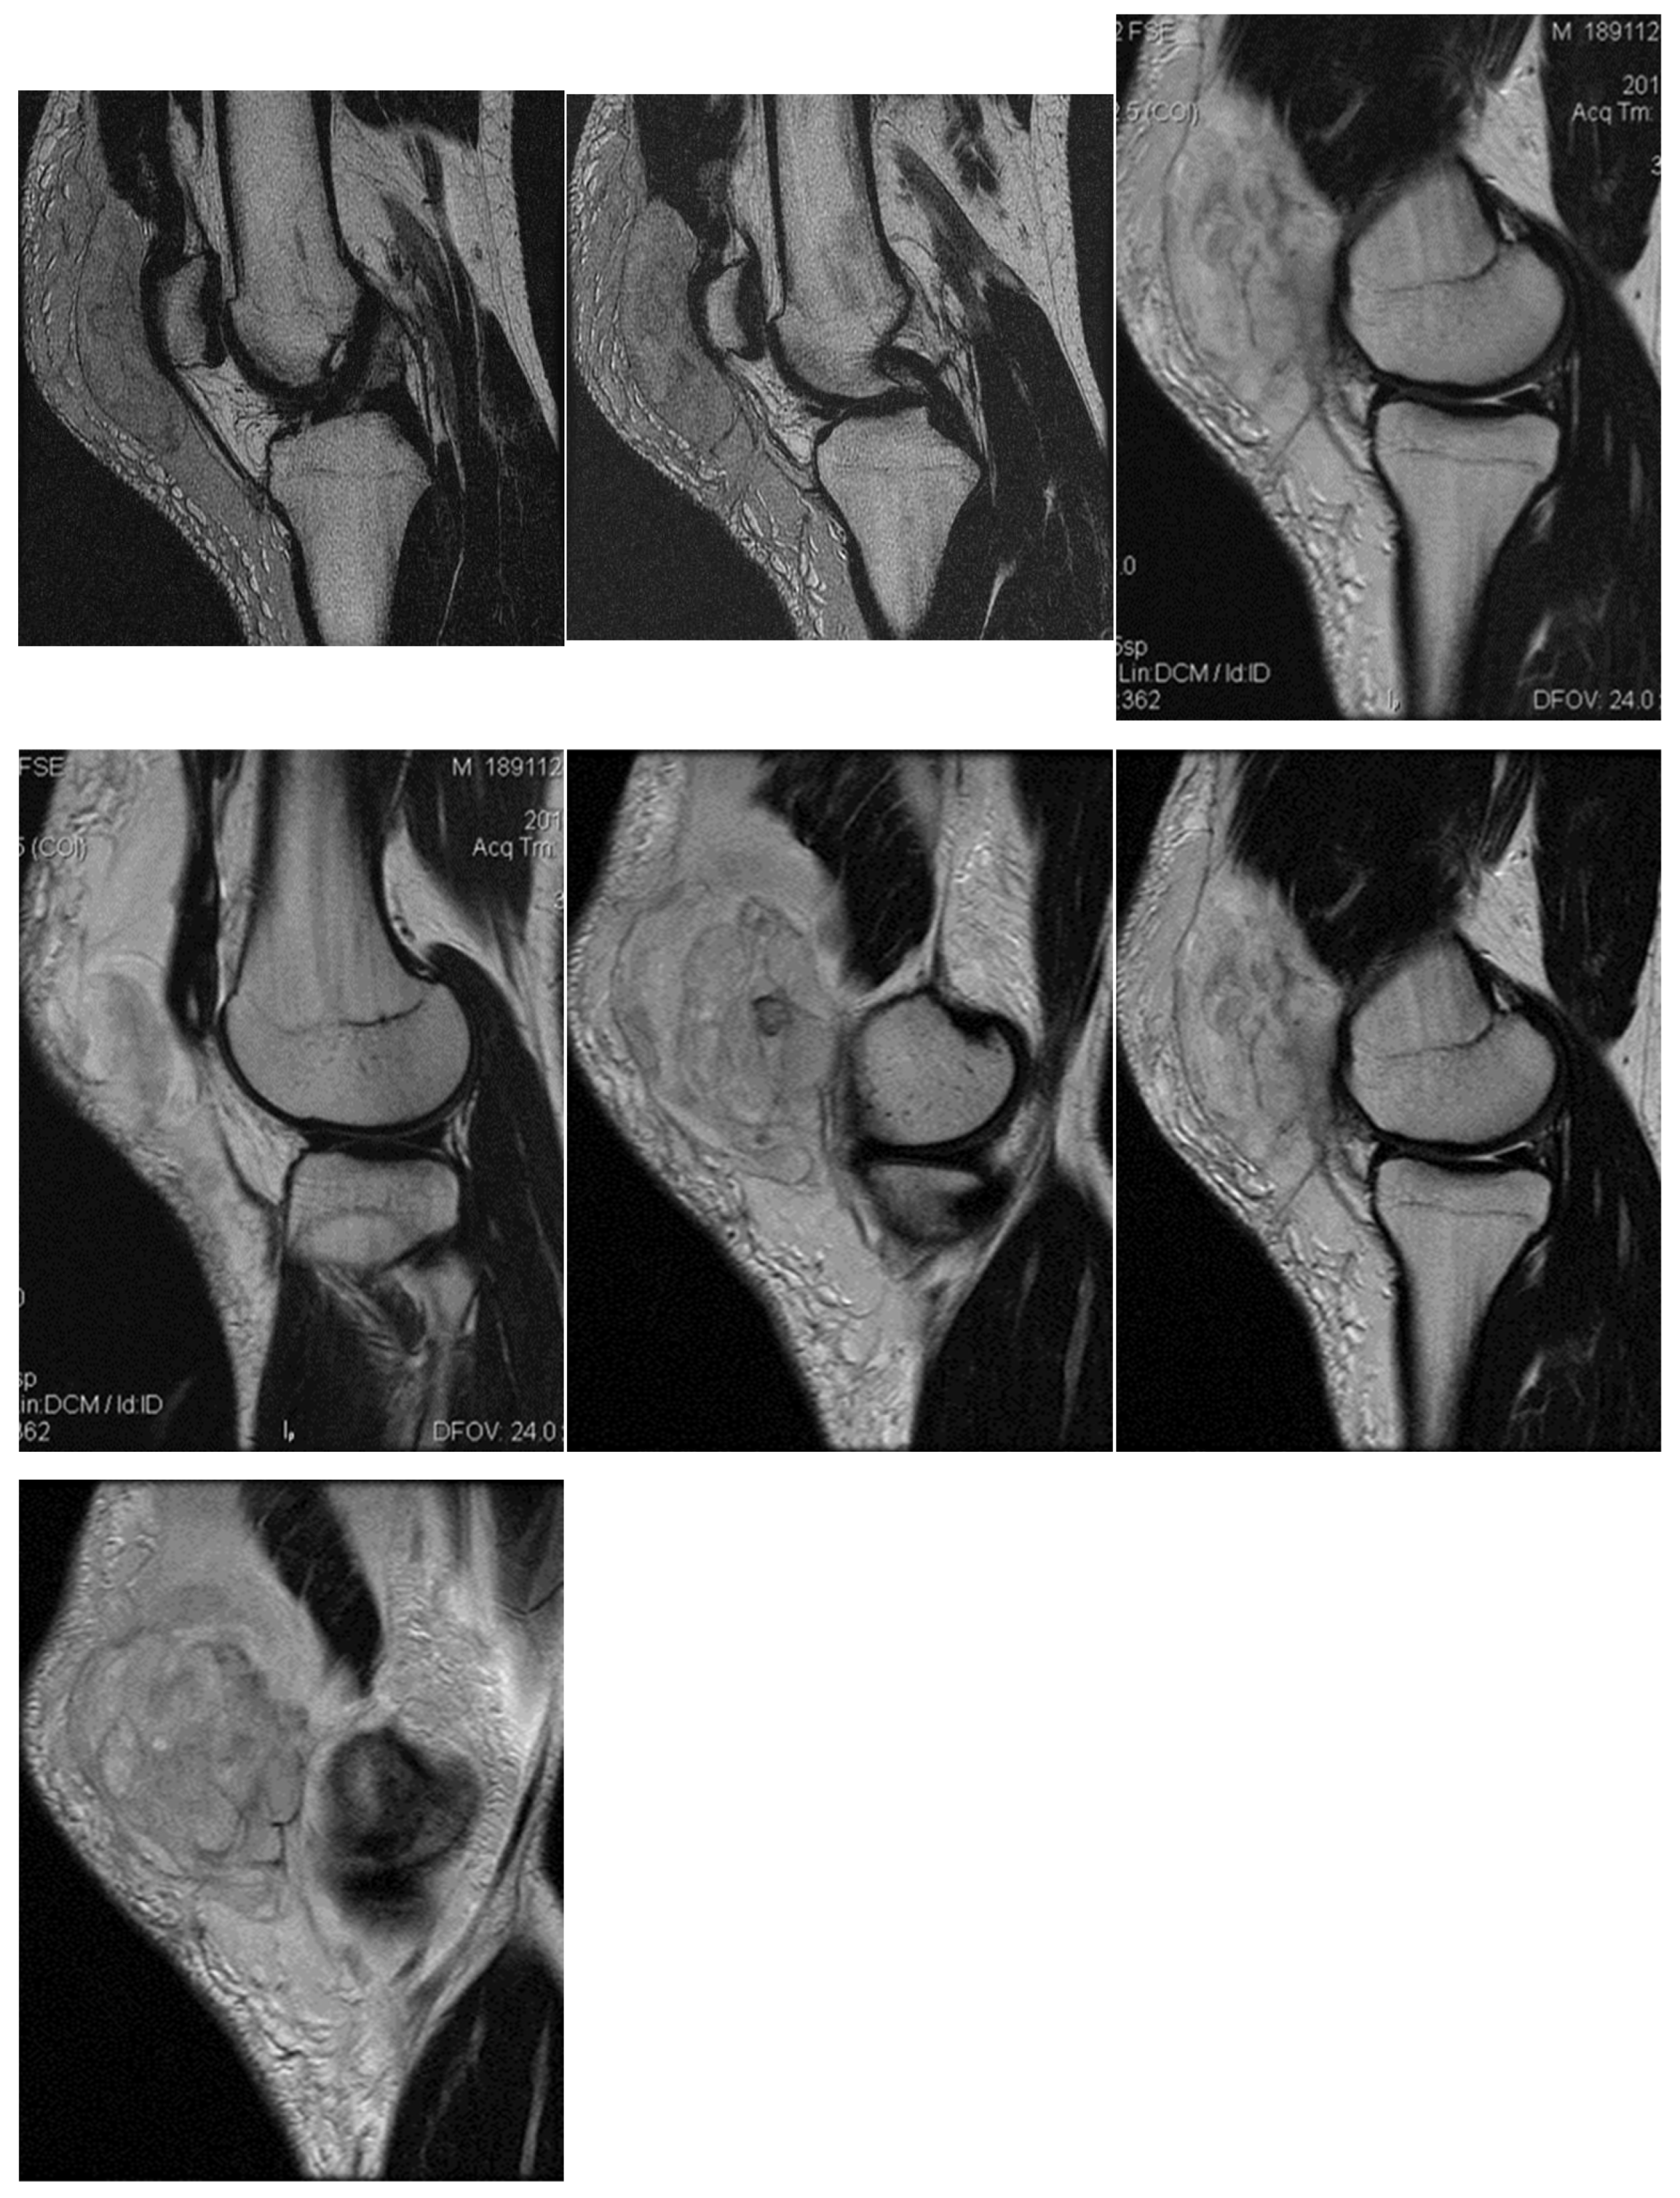

The spinal MRI revealed no evidence of degenerative lumbar disc pathology or radiculopathy (Figure 5). Magnetic resonance imaging (MRI) and radiographic examination of the pelvis revealed an old avulsion injury with a detached bone fragment at the insertion site on the left ischial tuberosity, involving the semitendinosus, semimembranosus, and biceps femoris muscles (collectively referred to as the ischium-calf muscles). This condition has led to the development of pseudoarthrosis and bone edema at the level of the ischial tuberosity. The sciatic nerve is positioned tangentially to the inflammatory response. Despite the detachment, the bone fragment remains vascularized due to the maintained insertion of the ischial calf muscles, preventing it from becoming a bone splinter (Figure 6 and Figure 7).

Figure 5.

(a) Spinal MRI: sagittal T2 fat sat acquisition, (b) spinal MRI: sagittal T2 acquisition, (c) spinal MRI: coronal T2 acquisition, (d) spinal MRI: axial T2 acquisition.

Figure 6.

(a) Pelvic MRI: coronal stir acquisition, (b) pelvic MRI: sagittal PD fat sat acquisition, (c) pelvic MRI: sagittal PD fat sat acquisition, (d) axial stir acquisition, (e) axial stir acquisition, (f) axial T1 acquisition.

The pseudoarthritis secondary to the old ischial tuberosity avulsion can be visualized as follows:

- An old detached bone fragment with signal in the T1 and T2 ponderations, similar to the rest of the existing bone structures, but showing focal alterations of the PD fat sac and STIR hypersignal, indicating bone edema.

- Fluid accumulation in T2 hypersignal, T1 hyposignal, between the torn bone fragment and the remaining tuberosity

- The altered PD fat sac hypersignal in the sciatic nerve, adjacent to the inflammatory process, indicates changes suggestive of focal neuritis.